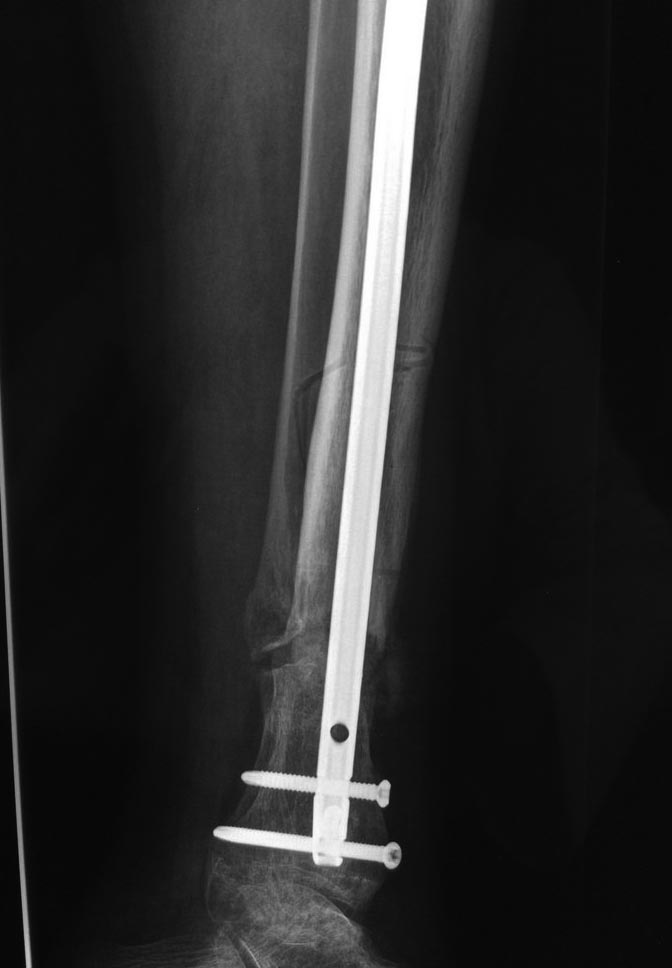

Уважаемые коллеги выразите Ваше мнение по следующему случаю.Молодой человек, 27 лет, находится на лечении с диагнозом: Ложный сустав большеберцовой кости в нижней трети, фиксированный интрамедуллярным блокированным стержнем (12.02.2014 г), ложный сустав малоберцовой кости в нижней трети левой голени, посттравматический артроз левого голеностопного сустава 1 стадии. Укорочение левой нижней конечности на 1,0 см. Со слов пациента известно, что в детстве получил перелом большеберцовой кости, лечился консервативно, перелом сросся с деформацией. Травма в июле 2010 г. бытовая-упал на лестнице, получил перелом малоберцовой кости, и перелом большеберцовой кости без смещения. Выполнена операция: Остеотомия большеберцовой кости в нижней трети, интрамедуллярный блокированный остеосинтез большеберцовой кости левой голени. Гладкое течение послеоперационного периода. Перелом большеберцовой кости сросся. Функция конечности восстановилась. В июне 2013 г выполнена операция удаление интрамедуллярного стержня из большеберцовой кости левой голени. Гладкое течение послеоперационного периода. Приступил к занятием физкультурой, бег. В августе 2013 г спрыгнул с автобуса, с чемоданом в руках, появилась резкая боль в левой голени. За медицинской помощью обратился через 7 дней, при обследовании выявлено: Рефрактура большеберцовой кости. Рекомендовано консервативное лечение в гипсовой повязке. В январе 2014 г. установлен диагноз: Ложный сустав большеберцовой кости в нижней трети, малоберцовой кости в нижней трети левой голени. Контрактура сгибательно - разгибательная левого голеностопного сустава. Посттравматический артроз левого голеностопного сустава 1 стадии. Укорочение левой нижней конечности на 1,0 см. В феврале 2014 г выполнил первым этапом: Фиксацию ложного сустава в АНФ с восстановлением осей сегментов. Через семь дней БИОС с рассверливанием. После операции - вальгус голеностопного сустава. Гладкое течение послеоперационного периода. Нагрузка по переносимости боли. Через 6 недель динамизация, через 2 недели стали мигрировать 2 фронтальных винта. Пытался подкрутить, пришлось удалить. Через 6 мес., контроль - линия ложного сустава прослеживается, но имеется периостальная костная мозоль. Не хватает стабильности.Вопрос что делать?Вариант № 1- выполнить реостеосинтез с рассверливанием КМК и на 12 мм диаметра гвоздь (стоит 11 мм)и убрать ротацию стопы руками одномоментно или одномоментно при помощи АНФ во время операции. Вариант № 2 выполнить удаление гвоздя, сделать все то же, что 6 месяцев назад, но с восстановлением анатомических взаимоотношений в голеностопном суставе.Вариант № 3 Двухэтапно, вторым этапом пластина на большеберцовую кость + костная пластика области не сращения.Вариант № 4 удаление гвоздя и лечение в КДА. Вопросы:1. Какой вариант оперативного лечения будет оптимальным в данном случае.2. При двухэтапной методике в дистальном отломке имеется канал от гвоздя, как направить гвоздь к наружному отделу дистального отломка большеберцовой кости. Есть опасения, что гвоздик может пойти по тому же каналу. Использовать поллер спицы или винты – сработают ли? И достаточна ли будет жесткость фиксации дистального отломка большеберцовой кости на гвоздике при 3 – 4 винтах при реостеосинтезе гвоздем.3. Нужен ли остеосинтез малоберцовой кости в нижней трети, с целью создания латеральной опоры. К сообществу за советом.

Здесь можно использовать все названные варианты. Гвоздь вполне тоже можно. Надо аппаратом восстановить длину и не повторять прежней ошибки - надо латеральную стенку сопоставить, а не оставлять наружного смещения. Да, надо ввести передне-задние спицы, чтобы не дать стержню попасть в старый канал. И длинной ручной разверткой лучше бы сформировать новый канал.

По поводу лечения, проблем правильной установки гвоздя не будет. Можно с помощью поллеров, которые помогут вывести в нужную траекторию. Но, если прежние попытки не привели к успеху, стоит ли тогда повторить неудачный опыт? Какая гарантия, что вальгусные силы не деформирует ось. Надо пересмотреть иллюзию, что гвоздь является идеальным фиксатором для решения данной патологии! Еще, при попытке подвести проблему под определенный фиксатор, результат получается неутешительным!

Из предложенных, я бы остановился на третьем варианте. Основная работа должна быть против вальгуса, и медиальная пластина для этой роли не подходит. Передний доступ, остеотомия большой и малоберцовой. Сагиттальная пила для артропластики толстая и не экономит кость. Полотно не более, чем 1.1 мм толщиной, создает идеальную поверхность остеотомии. Затем боковая компрессия-лагированием и передная пластина с костным графтом! Возможно, потеряет часть высоты, но наконец то возникнет сращение!